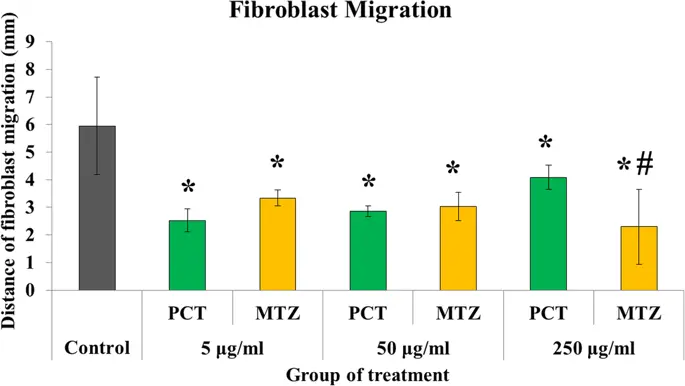

Миграция фибробластов ингибировалась в большей степени парацетамолом и метамизолом по сравнению с контрольной группой (р <0, 05) ( рис. 6 ). Ингибирование метамизола и парацетамола при миграции фибробластов было эквивалентным при дозах 5 мкг / мл (2, 34 ± 0, 29 против 2, 53 ± 0, 42 мм; р> 0, 05) и 50 мкг / мл (3, 04 ± 0, 51 против 2, 86 ± 0, 20 мм).; р> 0, 05), но эффект метамизола был выше в подавлении миграционной активности, чем парацетамол, при более высокой концентрации дозы 250 мкг / мл (1, 92 ± 1, 11 против 4, 08 ± 0, 44 мм; р <0, 05). Кроме того, парацетамол и метамизол не влияли на синтез коллагена фибробластов толстой кишки через 48 ч после операции по сравнению с контрольной группой при всех дозах лечения (р> 0, 05) ( рис. 7 ).

Среднее значение активности миграции фибробластов при различных обработках в течение 24 часов (PCT, парацетамол; MTZ, метамизол; *, PCT или MTZ против контроля, p <0, 05; #, PCT против MTZ, p <0, 05)

Эффект ингибирования метамизола был также замечен в миграции фибробластов. Это ингибирующее действие метамизола зависело от дозы и, по-видимому, является более доминирующим, чем парацетамол, при самой высокой дозе лечения. Согласно Nicpon et al. (25), влияние ингибирования метамизола на функцию клеток зависит от дозы. Чем выше концентрация, тем больше будет препятствий. Наши результаты показали аналогичные результаты, когда ингибирование миграции фибробластов увеличивалось с увеличением концентрации метамизола. Парацетамол, по-видимому, также оказывает негативное влияние на активность миграции фибробластов. Тем не менее, эффект не увеличился с добавлением дозы лечения. Ингибирование миграции фибробластов парацетамолом было еще меньше по сравнению с метамизолом в самой высокой дозе 250 мкг / мл. Эти результаты соответствовали предыдущим исследованиям, которые показали, что парацетамол является одним из НПВП, который обладает самым низким противовоспалительным эффектом. Ингибирование миграции фибробластов с помощью НПВП заключается в подавлении действия фермента циклооксигеназы. Эти эффекты могут быть восстановлены введением экзогенных простагландинов (26). Кроме того, механизм ингибирования миграции фибробластов осуществляется через путь фермента матричной металлопротеиназы, известный как RECK (белок, индуцирующий реверсию, богатый цистеином с мотивами Kazal) (27).